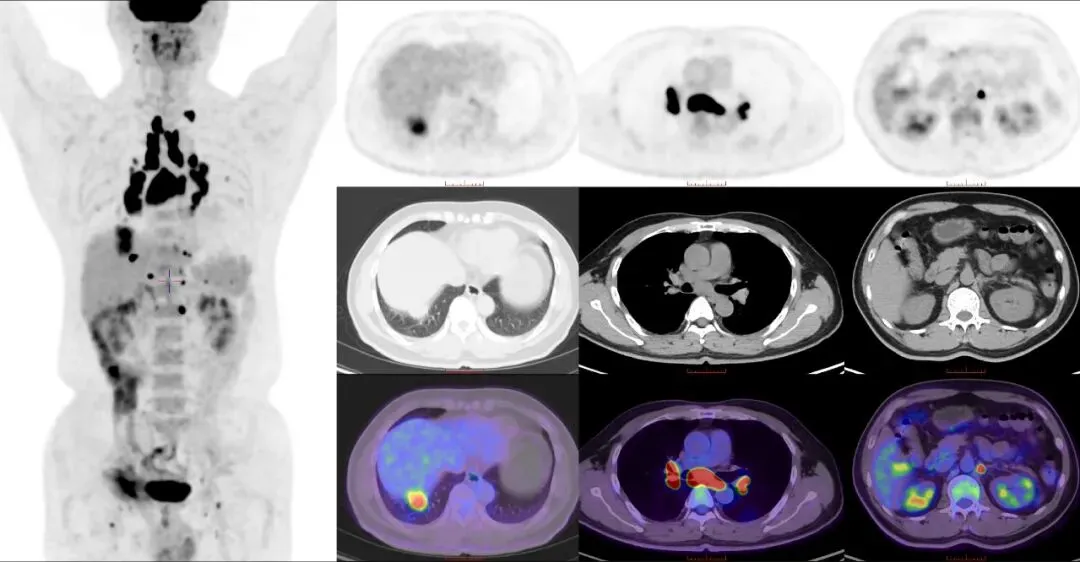

CASE 4

男,53岁,发现肺部阴影6天。患者于6天前在我院行疝气修补时行胸部CT示:右下肺隔上结节伴纵隔、肺门多发肿大淋巴结,需考虑恶性病变(周围型肺CA并淋巴结转移)可能,请结合临床穿刺分析。我院18F-FDG PET/CT示右肺下叶实性结节,糖代谢异常增高;左锁骨上窝、双肺门及纵隔、腹膜后多发淋巴结,糖代谢增高。